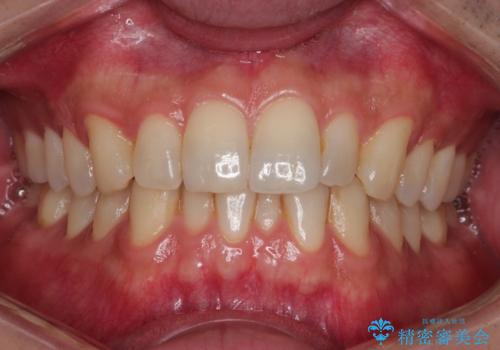

初診時の歯並びの状態としては、下顎に中等度のがたつき(叢生)がある状態でした。

抜歯は行わず下顎の奥のスペースを利用して歯をスライドする方法の他に親知らずの抜歯そして上下ともに歯列弓の拡大やディスキング(歯と歯の間の隙間を作る処置)を行い叢生を改善しました。

歯の大きさの不揃いが原因の正中のズレは、ディスキング量を調整することで合わせました。